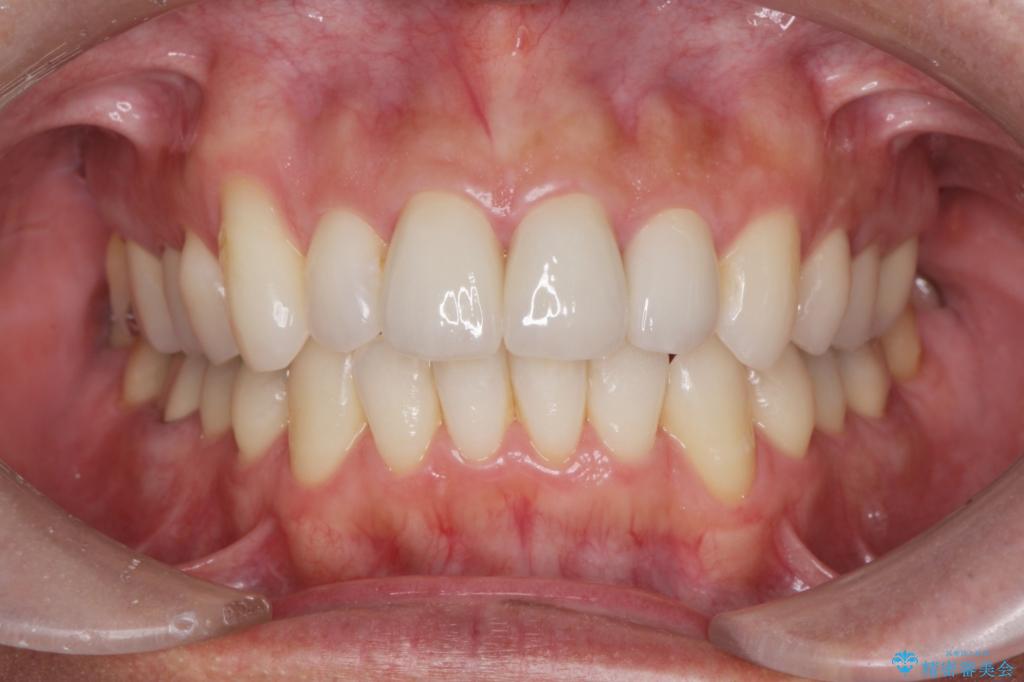

矯正と虫歯のセラミック治療 総合歯科治療の実践

- 突き出た前歯の角度の改善と虫歯治療の改善を求めて来院されました。

虫歯を除去したのち、マウスピース矯正治療を行い、歯並びやがたつきを改善したのち、セラミックに置き換えることで審美性の向上を計画します。